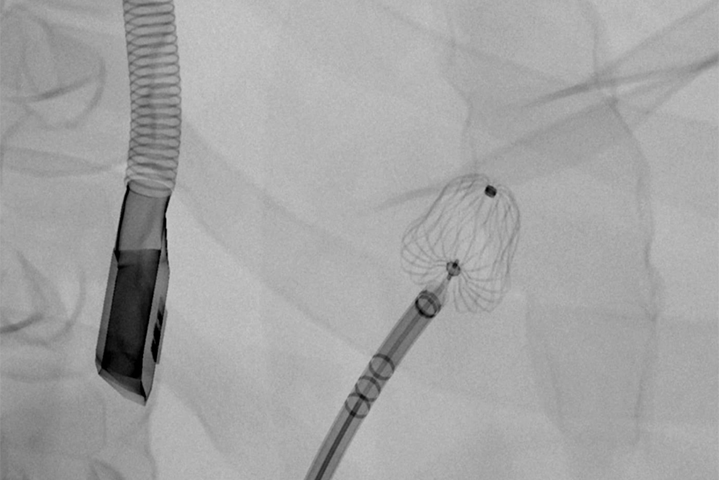

Virtual Reality simulators for image-guided interventional therapies

Our anatomical software physics engine, combined with haptic-enabled hardware solutions, creates the optimal environment for procedural adoption, proficiency-based training, patient-specific simulation, and objective skills assessment. Over 350 development years of engineering have created the most advanced IGIT simulation solutions on the market.

Over 2000+ systems delivered worldwide that cover fluoro & echo based learning solutions from head to toe for both Healthcare Professionals and the MedTech Industry.